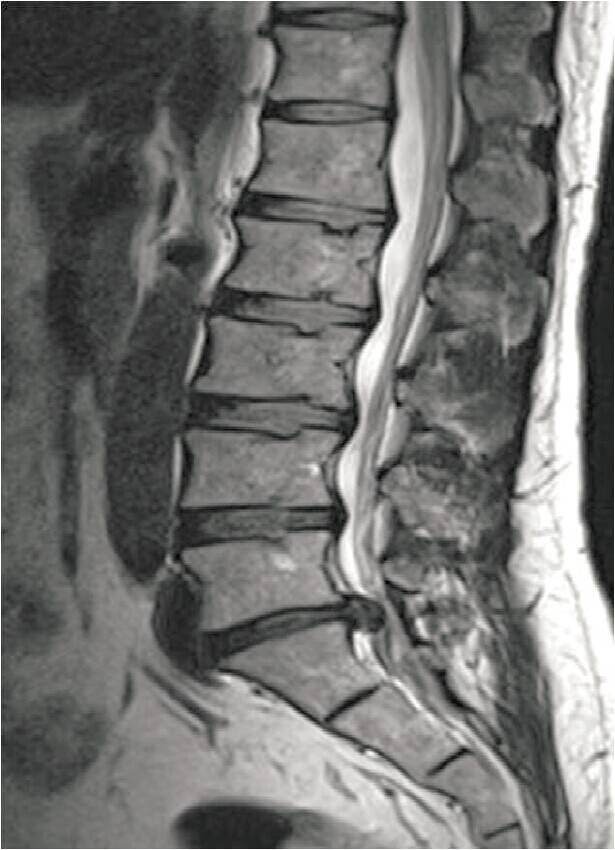

MRI: 腰5骶1 (L5〜S1)椎间盘突出。

下图为:术前MRI L5~S1椎间盘突出